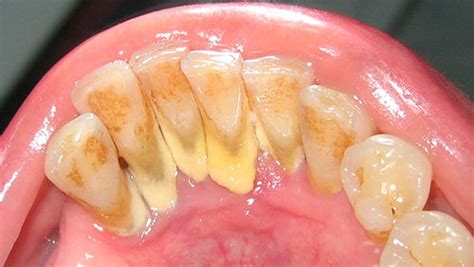

Cuando no se erradica a tiempo, el sarro puede acumularse sobre y/o entre los dientes. A diferencia de la placa que es una película incolora, el sarro presenta minerales siendo fácilmente visible si se localiza por encima de la línea de las encías. El indicador de sarro más común es observar un color marrón o amarillento en los dientes o encías.

Ejemplo de sarro dental visible en los dientes.